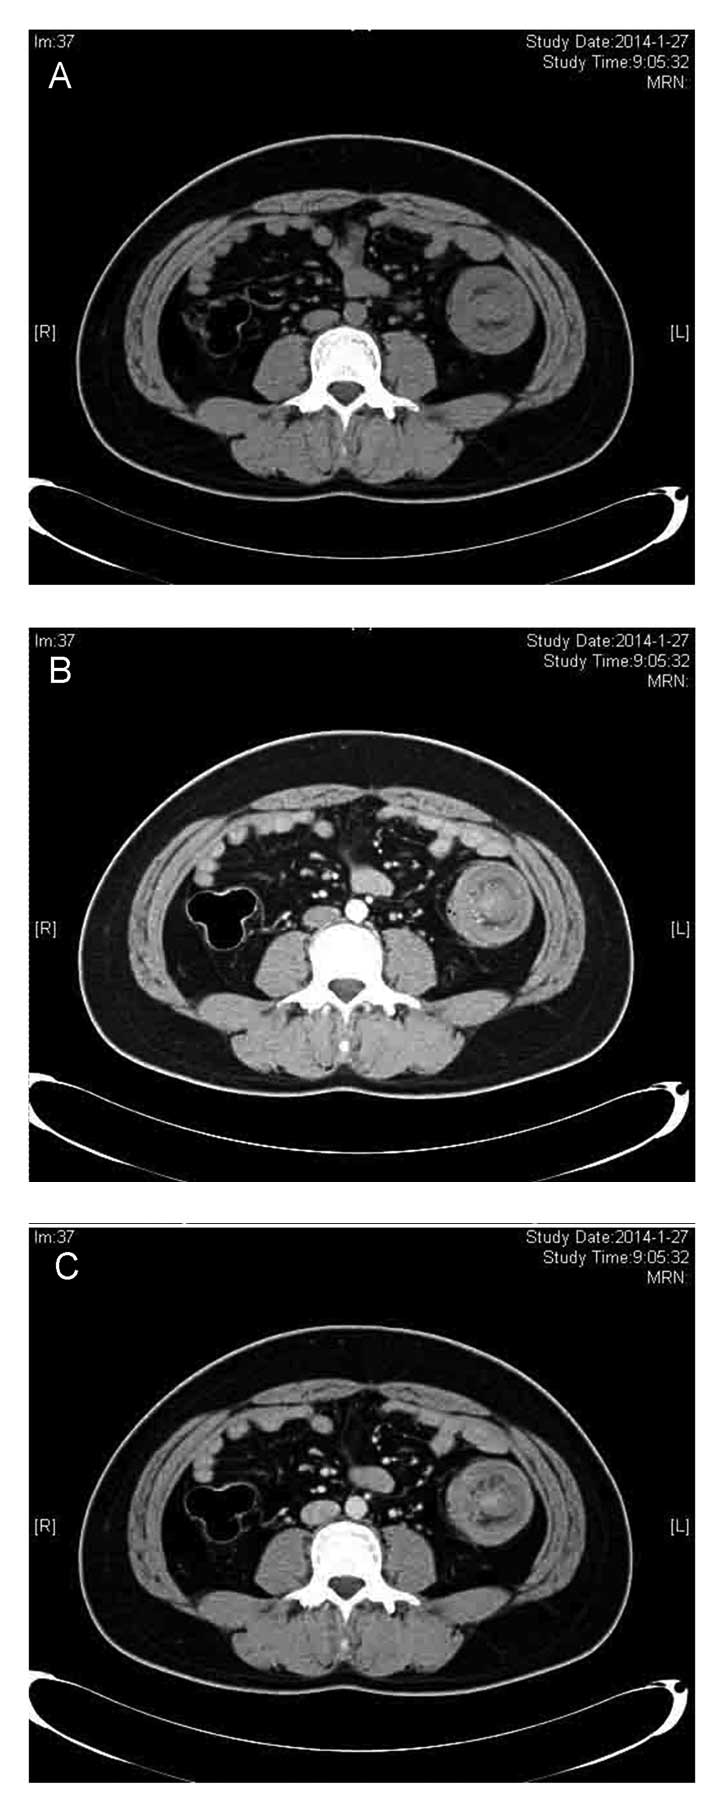

Descending colo-colonic intussusception secondary to signet ring cell carcinoma: A case report

The incidence of intussusception is low in adults, particularly in the descending colon, due to the anatomical attachment of the descending colon to the retroperitoneum. Signet ring cell histology represents ~1% of colon adenocarcinomas and is associated with young patients and a poor clinical outcome. The present study describes a case of descending colo‑colonic intussusception caused by signet ring cell carcinoma in a 27‑year‑old male. The patient presented with a history of intermittent left upper‑quadrant abdominal pain for more than six months without any evident etiology. A computed tomography scan of the abdomen revealed left‑sided colo‑colonic intussusception. Upon laparotomy, a left hemicolectomy was performed according to intraoperative frozen‑section pathology. Post‑operative pathological evaluation revealed signet ring cell carcinoma invasion of the serosa, and 31.8% (7/22) of the regional lymph nodes were positive for cancerous cells. The post‑operative course was uneventful and the patient was discharged on the tenth post‑operative day.